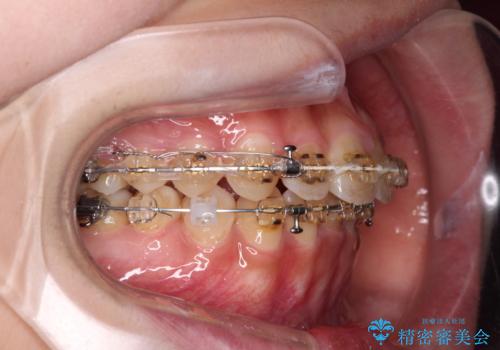

- 矯正装置

- 審美装置

- 2年6ヶ月

舌の突出癖の影響か、なかなかスペースが閉じきらず、治療期間は予定よりも長期間となりました。

舌突出癖改善のトレーニングの重要性を認識することとなりました。